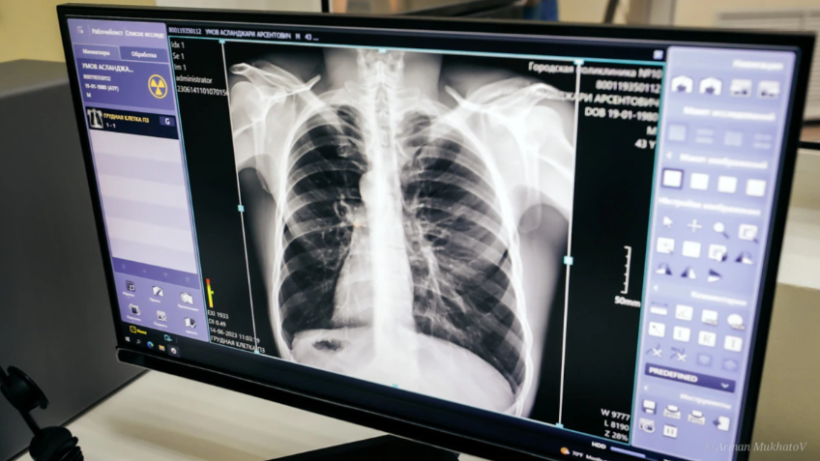

Атырау облыстық денсаулық сақтау басқармасының баспасөз қызметінен мәлім еткендей, науқасқа «Екі өкпенің инфильтративті туберкулезі, ыдырау сатысы» деген диагноз қойылған.

Науқас өкпе туберкулезімен 1992 жылы сырқаттанып, емделген. 1992 жылы оң жақ өкпесінің жоғарғы бөлігіне резекция операциясы жасалған. Емдеудің нәтижесінде сырқатынан сауығып шыққан, - деп хабарлады басқарманың баспасөз қызметі.